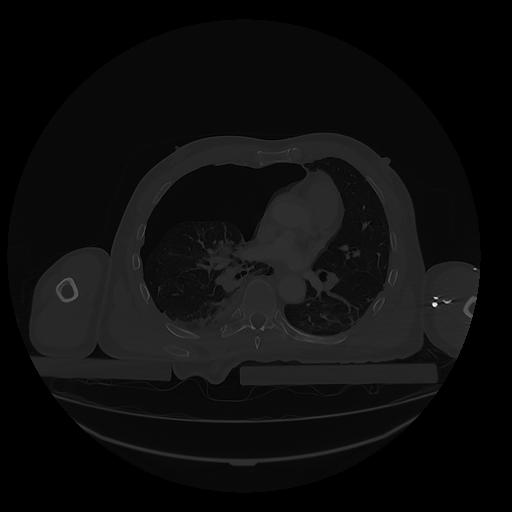

31 PULMON,CE,Vol,1.0,PULMON,,